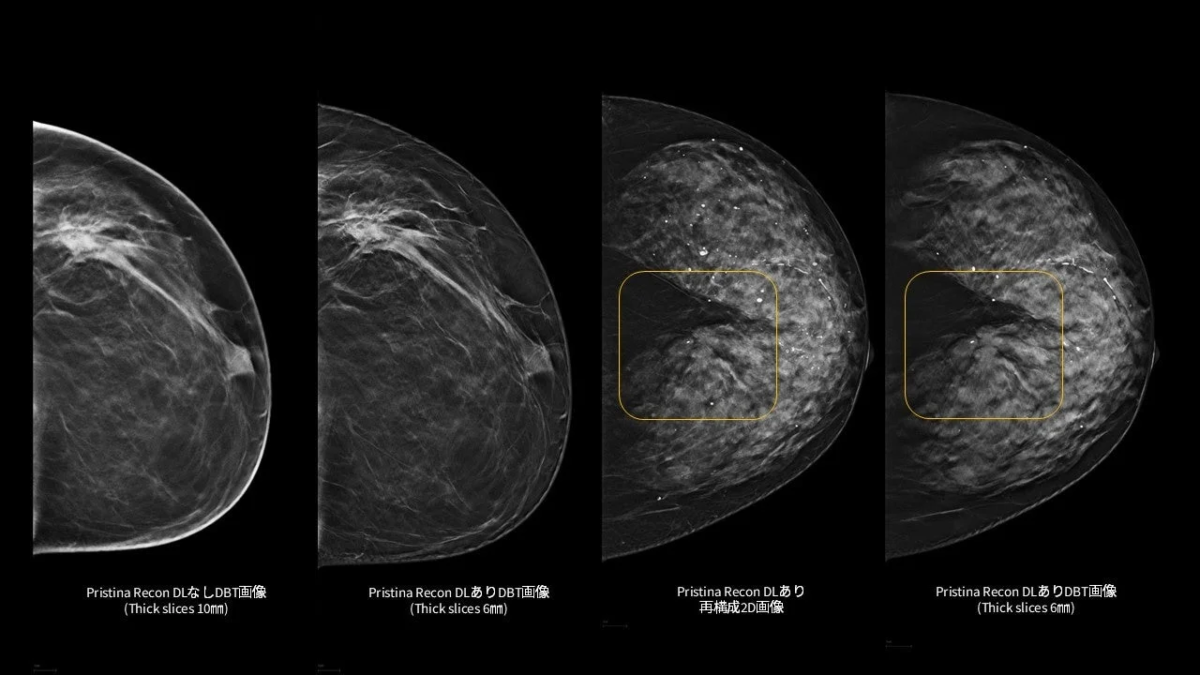

「Pristina Recon DL」は、これらの技術的特徴により、3Dマンモグラフィおよび再構成2D画像の双方において、読影に必要な情報をより明確に可視化し、診断を支援する読影環境の向上に貢献します。

Pristina Recon DLの有無やスライス厚が異なる乳房画像を比較。DLありの画像はよりクリアで詳細な情報が確認できる。